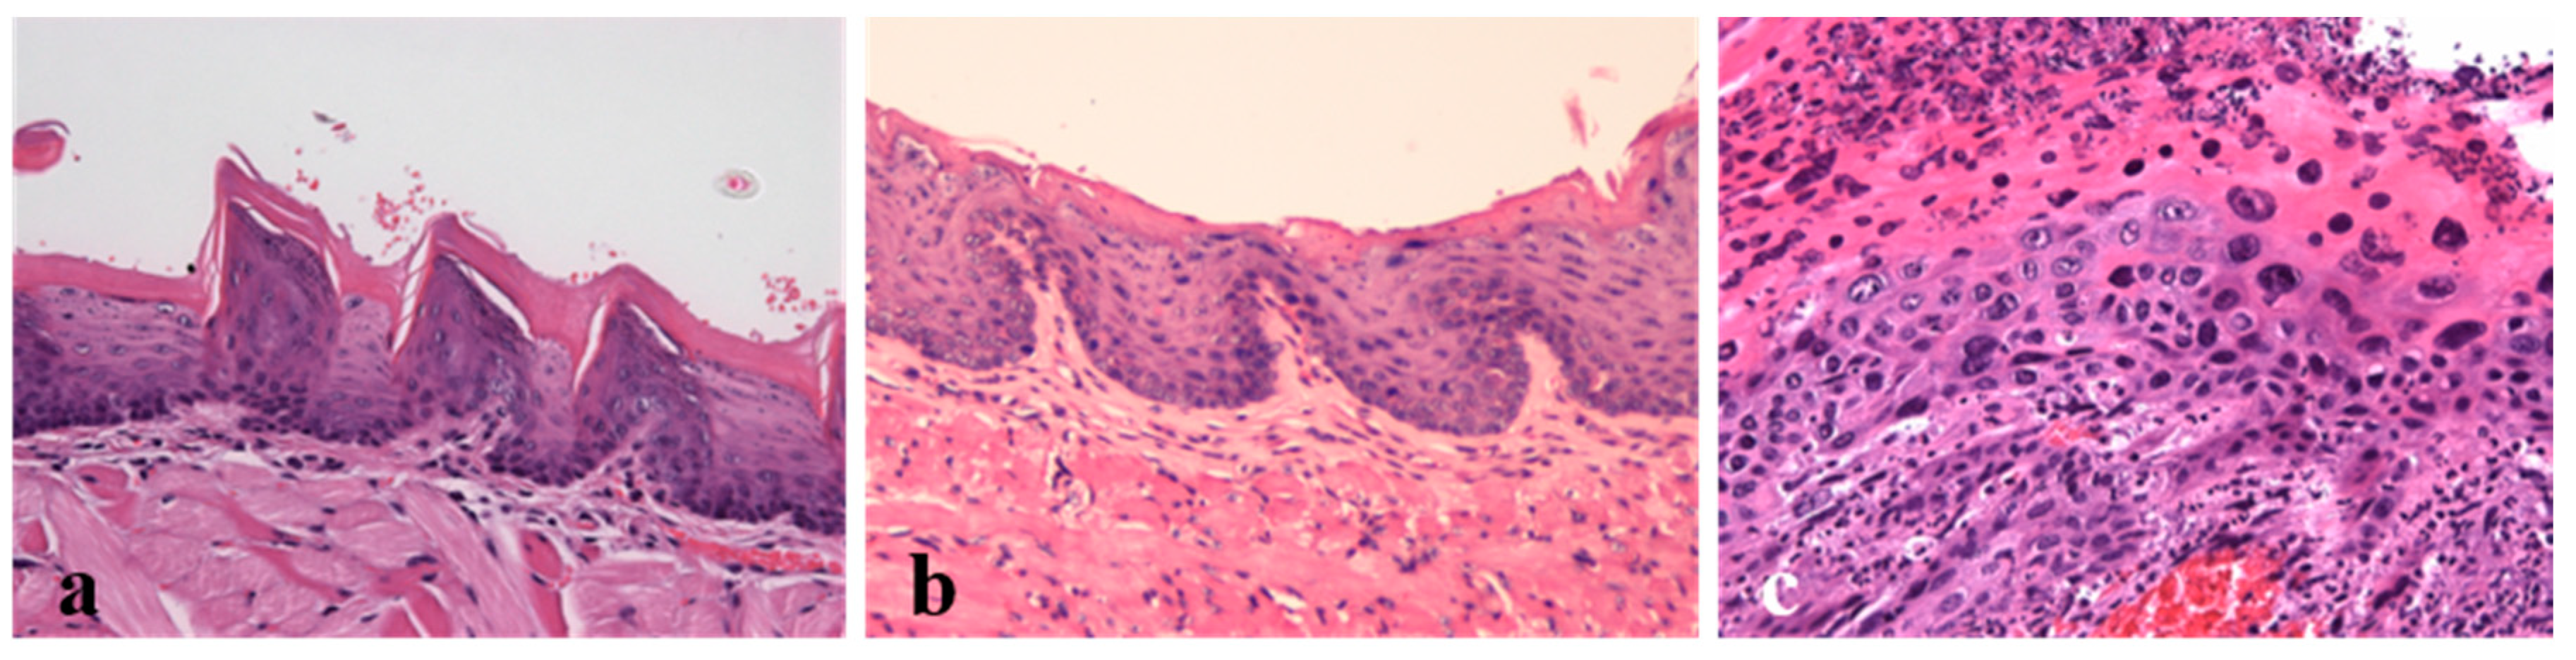

2.3. Histological Analysis

4.4. Histological Anlysis

| 3 (HPV+ without DMBA application, n = 10) | Chest skin | 0/10 (0%) | 10/10 (100%) | 0/10 (0%) | 0/10 (0%) |

| Ear skin | 0/10 (0%) | 8/10 (80%) | 2/10 (20%) | 0/10 (0%) | |

| Penile | 2/10 (20%) | 7/10 (70%) | 1/10 (10%) | 0/10 (0%) | |

| Tongue | 1/10 (10%) | 4/10 (40%) | 4/10 (40%) | 1/10 (10%) | |

| 4 (HPV+ with DMBA application, n = 10) | Chest skin | 0/10 (0%) | 3/10 (30%) | 7/10 (70%) | 0/10 (0%) |

| Ear skin | 0/10 (0%) | 2/10 (20%) | 7/10 (70%) | 1/10 (10%) | |

| Penile | 0/10 (0%) | 2/10 (20%) | 8/10 (80%) | 0/10 (0%) | |

| Tongue | 0/10 (0%) | 9/10 (90%) | 1/10 (10%) | 0/10 (0%) | |